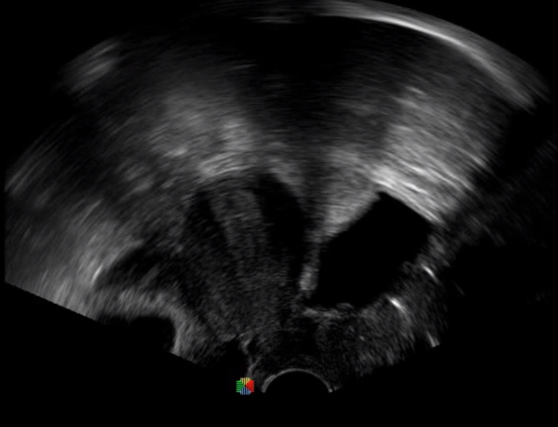

TEE(經(jīng)食道超聲心動(dòng)圖)將超聲探頭置入食道內(nèi),從心臟的后方向前近距離探查其結(jié)構(gòu) ,克服了經(jīng)胸超聲檢查的局限性,避免肺內(nèi)氣體、胸壁脂肪、胸廓畸形等因素影響,觀察角度更多,圖像更加清晰,測(cè)量數(shù)據(jù)更準(zhǔn)確。

經(jīng)食道超聲 大動(dòng)脈短軸